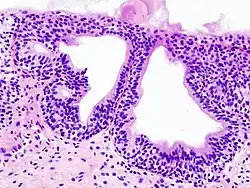

Cystitis glandularis

Cystitis glandularis is the transformation of mucosal cells lining the urinary bladder. They undergo glandular metaplasia, a process in which irritated tissues take on a different form, in this case that of a gland.[1] The main importance is in the findings of test results, in this case histopathology. They must distinguish a benign metaplastic change from the cancerous condition urothelial cell carcinoma.[2] It is a very common finding in bladder biopsies and cystectomies, and most often found in the trigone area. Cystitis glandularis lesions are usually present as small microscopic foci; however, occasionally it can form raised intramucosal or polypoid lesions. The cystitis glandularis lesions are within the submucosa.

There are two main types of cystitis glandularis, non-mucinous and mucinous (intestinal). The difference is in the cellular production of mucin, a normal feature of colonic and intestinal epithelial cells but not of urothelial cells.[3] Another distinction is made between focal areas and diffuse involvement of the bladder. Whereas focal areas are more common, diffuse involvement is seen in chronically irritated bladders, such as in paraplegics or those with bladder stones or indwelling catheters. Individuals with diffuse intestinal-type cystitis glandularis are at increased risk for developing bladder cancer.

Cystitis glandularis arises from and merges with Von Brunn's nests, which are groups of urothelial cells (cells of urinary tract) within the lamina propria and submucosa, formed from budding from the surface mucosa. They are considered normal. Cystitis cystica is a similar lesion to cystitis glandularis, where the central area of the Von Brunn's nests have degenerated, leaving cystic lesions. Other metaplastic entities in the urinary bladder include squamous metaplasia and nephrogenic adenoma.